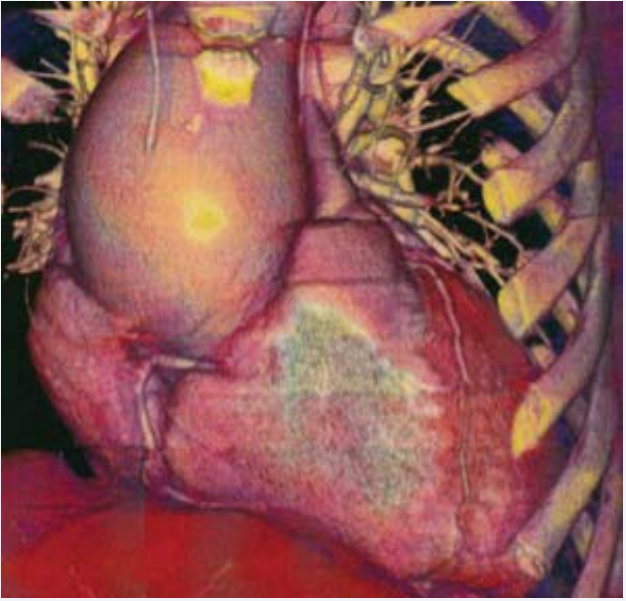

In this context, the patient underwent surgical resection of the aneurysm (Figure 5a),

Picture of the ascending aortic aneurysm in the operating  room.

Figure 5a: Picture of the ascending aortic aneurysm in the operating room.